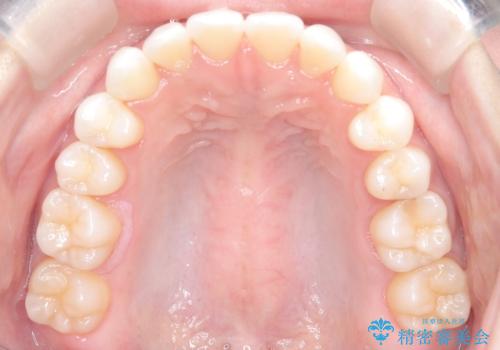

【インビザライン】前歯の凸凹をマウスピース矯正でなおしたい

- 前歯の凸凹を主訴に来院されました。

上の前歯は翼状捻転と呼ばれる状態でしたが、奥歯の遠心移動を行うことで配列スペースを確保することで綺麗に歯を並べることができました、

途中でインビザラインの使用時間が短くなってしまったため期間が予定より少し伸びましたが、1年半で満足いく結果となり患者様に喜んでいただけました。